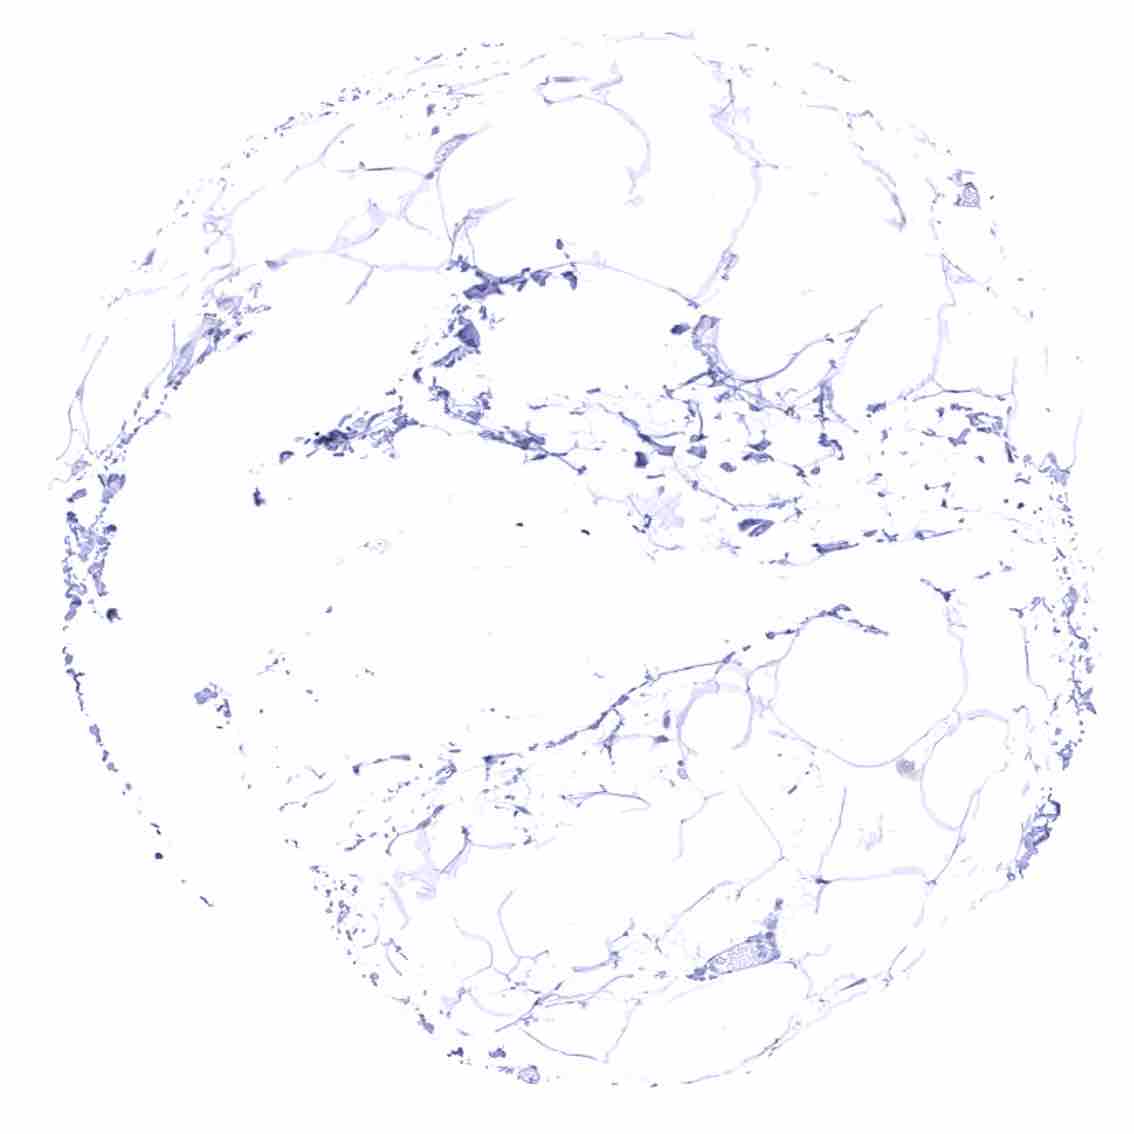

Fat